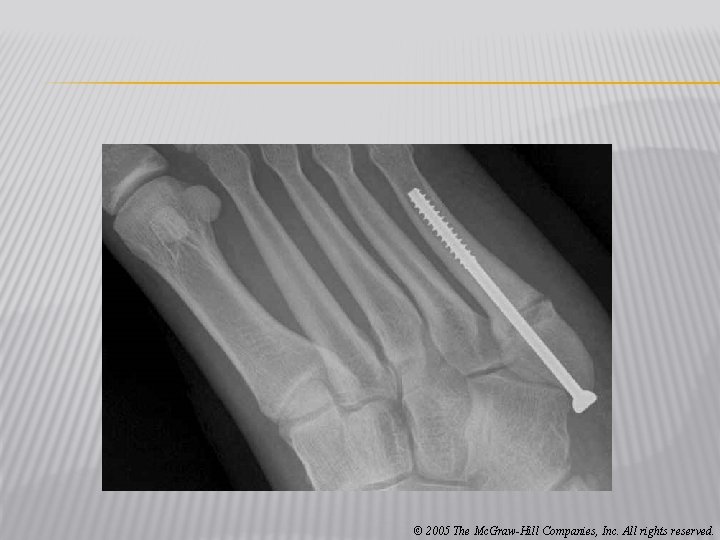

� Jones Fracture � Cause of Injury � Fracture of metatarsal caused by inversion or high velocity rotational forces � Most common = base of 5 th metatarsal � Sign of Injury � Immediate swelling, pain over 5 th metatarsal � May feel a “pop” � High nonunion rate and course of healing is unpredictable � Care � Generally requires 6 -8 weeks non-weight bearing with short leg cast if non-displaced � If nonunion occurs, internal fixation may be required © 2005 The Mc. Graw-Hill Companies, Inc. All rights reserved.

© 2005 The Mc. Graw-Hill Companies, Inc. All rights reserved.